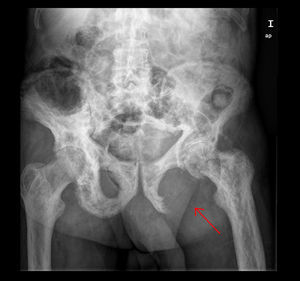

Presentamos el caso de un paciente varón de 82 años diagnosticado 10 años antes de enfermedad de Paget ósea con afectación poliostótica. Como otros antecedentes de interés presentaba fibrilación auricular e insuficiencia cardiaca crónica. Acudió a la unidad y consulta de atención inmediata (UCAI) por astenia, anorexia y edemas en las extremidades inferiores de 15 días de evolución. En la anamnesis por aparatos refería dolor en la región isquiopubiana izquierda desde hacía 6 meses, que había ido en aumento y que aparecía tanto en reposo como con el ejercicio. Se decidió ingreso en planta de hospitalización para tratamiento de la insuficiencia cardiaca y estudio del origen del dolor. En la exploración física presentaba palidez de piel y mucosas, auscultación cardiaca irregular con soplo sistólico aórtico, disminución generalizada del murmullo vesicular en la auscultación pulmonar, edema con fóvea hasta la raíz de ambos miembros inferiores y dolor a la movilización e impotencia funcional de articulación coxofemoral izquierda. En el tacto rectal no se encontraron masas y existían restos de heces normales. En la analítica destacaba hemoglobina de 9,5g/dl con volumen y hemoglobina corpuscular media normales, proteína C reactiva: 21,2mg/dl (0,2-0,8), fibrinógeno: 722mg/dl (200-400), velocidad de sedimentación glomerular: 120mm (1-15), fosfatasa alcalina: 155 U/l, hierro: 23,6μg/dl (50-150) transferrina: 155μg/dl (300-360), ferritina: 1.144μg/l (50-350), índice de saturación: 12% (20-40), receptor soluble de transferrina: 7,88μg/l (2-4); los marcadores tumorales eran normales. En la radiografía de tórax presentaba derrame pleural bilateral de escasa cuantía y lesiones compatibles con enfermedad de Paget en ambos hombros y el quinto arco costal izquierdo. La radiografía de pelvis mostró múltiples lesiones compatibles con enfermedad de Paget y una imagen lítica de mayor tamaño en isquion izquierdo (fig. 1). Se realizó una gammagrafía ósea que mostró imágenes compatibles con enfermedad de Paget y ausencia de captación en isquion izquierdo (fig. 2). Se solicitó una tomografía computarizada toraco-abdómino-pélvica que objetivó una gran masa de contornos lobulados con focos de calcificación que destruía el isquion y acetábulo izquierdo de 12 x 12 x 16cm (fig. 3). Ante la sospecha de neoplasia ósea sobre enfermedad de Paget se realizó una biopsia de hueso iliaco cuyo estudio fue compatible con un sarcoma pleomórfico indiferenciado de alto grado no osteogénico, vimentina positivo, con coexpresión de CD-68 y mínima expresión de actina y desmina. La evolución del paciente fue desfavorable, con gran afectación del estado general y dificultad para controlar el dolor, se decidió iniciar tratamiento con radioterapia para control fundamentalmente sintomático. Finalmente, el paciente falleció a la semana del diagnóstico anatomopatológico.